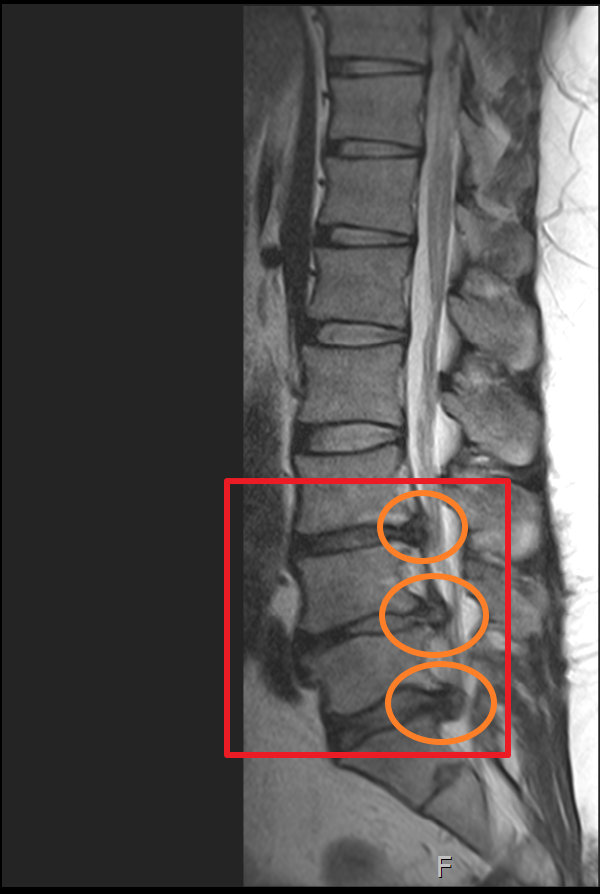

마지막으로 제가 촬영했었던 MRI 촬영 이미지를 첨부해 볼까 합니다. 이미지 순서대로 2014년, 2018년, 2020년 촬영했던 MRI 사진입니다. MRI 촬영 당시 허리디스크 상태가 좋지 않은 상황에서만 세 차례 찍었던 것이기에 이점도 고려해서 참고하시면 좋을 듯합니다.

이미지를 보시면 빨간색 네모 칸에 하얀색 기다란 세로 라인이 신경이 지나가는 부분이며 가장 바깥쪽 두꺼운 흰색 부분은 배 쪽의 지방입니다.

2020년 첫번째, 두번째 터졌던 허리디스크가 많이 흡수되어 신경을 누르고 있는 디스크 압박이 많이 좋아졌으나 세번째 허리디스크가 터진 곳이 심해진 상황.

마지막 허리디스크 MRI는 2020년에 촬영했습니다. 마찬가지로 사진을 보시면 최초 발병한 허리디스크 첫 번째 동그라미는 흡수가 된 게 눈에 보일 정도였으나 4년뒤엔 두 번째 동그라미와 세 번째 동그라미 디스크가 많이 튀어나와 신경을 누르고 있는 게 보입니다.

하지만 MRI 상 표시된 부분을 보면 첫 번째 허리디스크가 튀어나왔던 부분이 흡수된 게 확실히 보이며 이제는 다른 부분에 허리디스크가 눌려 신경을 누르고 있는 게 보입니다.

MRI에 표시된 부분만 놓고 본다면 허리에 데미지를 주지 않고 잘 관리하는 상황에서 분명 튀어나온 허리디스크가 흡수 되는 건 맞는 이야기이며 허리디스크가 흡수되는 시간이 최소 6개월 이상으로 굉장히 오래 걸린다는 겁니다.